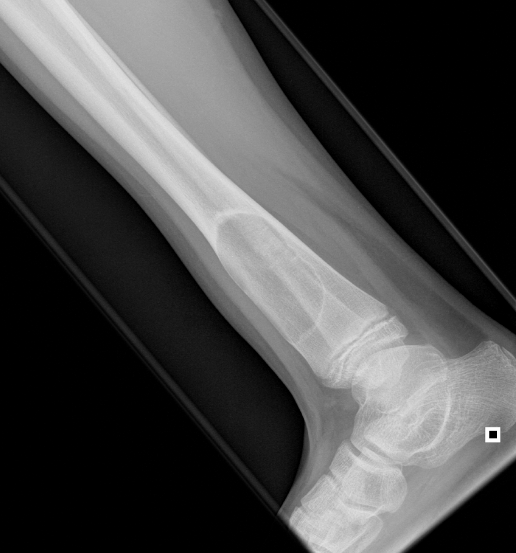

3. Non Ossifying Fibroma